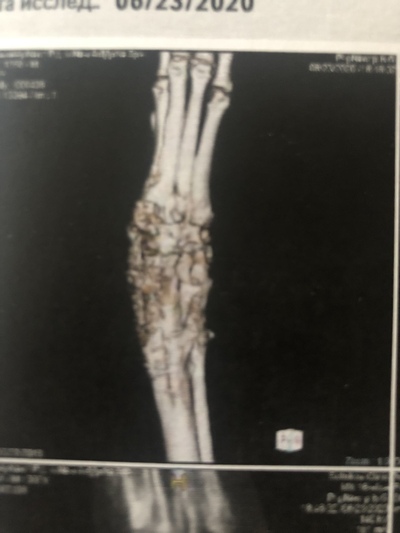

Но несмотря на заметные глазу улучшения, рентгены говорили об обратном. Местные вет врачи, а также многочисленные консультации с лучшими московскими и питерскими клиниками сводились к одному - остеомиелит, проще говоря, кость разрушалась, а не срасталась. На фото рентген спустя 3 месяца после операции

И спустя еще один месяц результат был примерно тот же

С момента операции прошло уже больше 4 месяцев, результата сращивания кости нет, здоровье молодой лошади сильно подорвано антибиотиками, состояние почек можно назвать как "не сегодня, так завтра откажут". Артроз скакательного сустава больной ноги был диагностирован по рентгенам (из-за того, что слишком долго сустав бы зафиксирован гипсом), артроз всех здоровых ножек виден уже снаружи. Не говоря уже о менее значительных изменениях, таких как сутулая спина, зажатые забитые мышцы всего тела, потеря веса